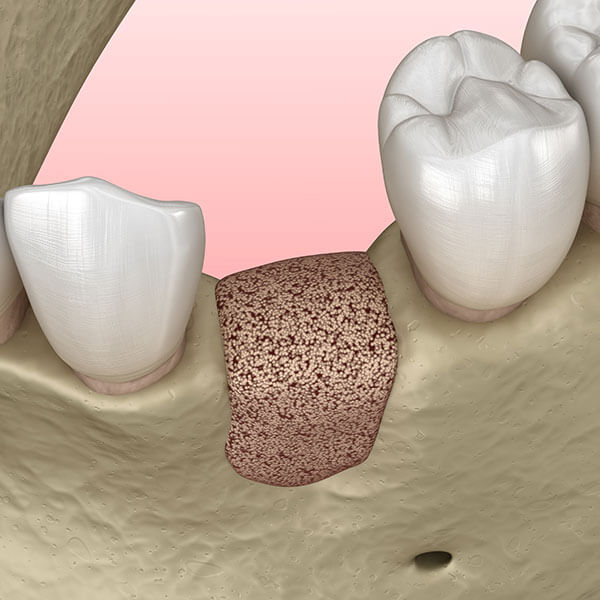

骨造成(GBR)とは?

骨造成(GBR)

上の歯は、上顎骨の中に埋まっていますが、奥歯の歯根の先には上顎洞という空洞があります。

上の奥歯にインプラントを埋入する際、深さが足りない場合空洞に突き抜けないように空洞粘膜を持ち上げ骨を増やす手術をします。

その方法が、サイナスリフト、ソケットリフトで高度なテクニックを必要とする治療法です。

サイナスリフト 上の顎の横から上顎洞に穴を開けて、上顎洞粘膜を剥離し持ち上げ、そこへ人口骨、骨補填材を入れる方法です。

ソケットリフト 上の顎に下から小さな穴を開けて、そこから少しずつ人口骨、骨補填材をゆっくり入れていく方法です。